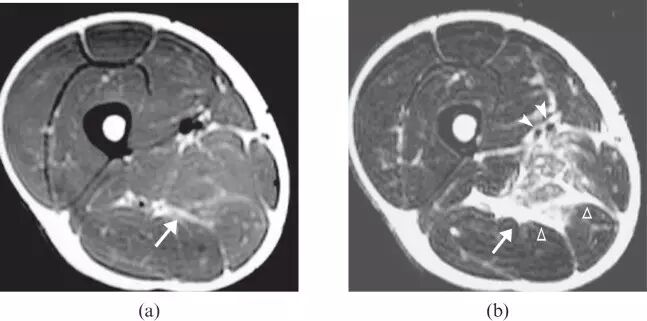

图10.34岁男性传染性肌炎,HIV阳性,右四头肌肌肉(星号)中表现为水肿,其呈现出肿胀的疼痛大腿和发烧。 值得注意的是,没有脓肿形成,但MR图像上看到包块的形态。

![]()